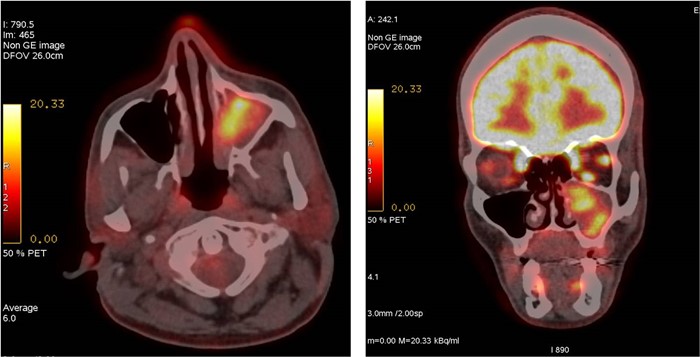

Diagnostyka obrazowa zatok staje się coraz bardziej istotna dla lekarzy dentystów, którzy posiadają w swoich gabinetach aparaty tomografii stożkowej (CBCT). W zależności od wielkości pola obrazowania w CBCT są widoczne fragmenty zatok szczękowych aż po całe zatoki szczękowe, a w badaniach o największym polu obrazowania wszystkie zatoki oboczne nosa, podobnie jak w badaniu medycznej tomografii komputerowej (TK). Z tego względu celem pracy jest przedstawienie najważniejszych zmian patologicznych zatok szczękowych, z którymi może się spotkać lekarz stomatolog, opisując badania tomografii stożkowej (CBCT).